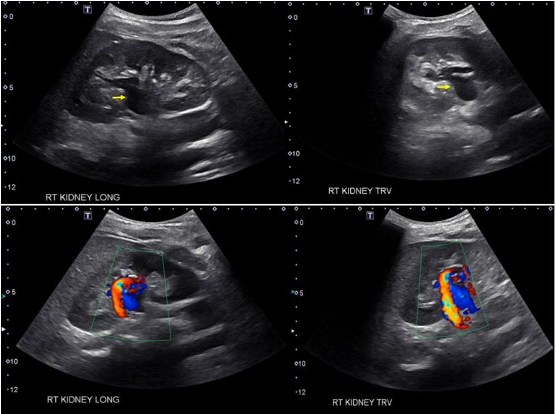

Prominent renal vasculature: Anechoic central regions may mimic hydronephrosis. Apply color doppler to differentiate — vessels will show flow [6].

Figure 5. Vascular Malformation [6].